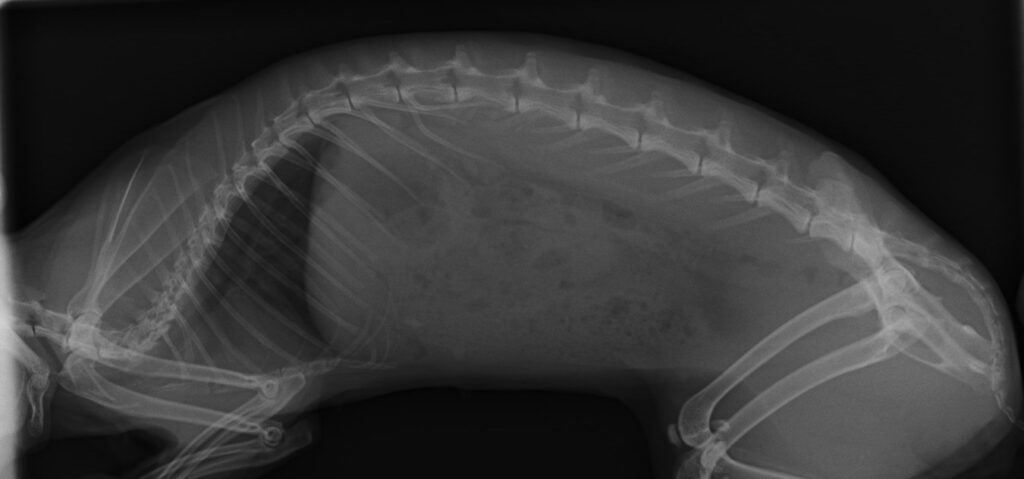

そしてレントゲンです。

前後と左右、二方向撮影します。

心臓の大きさ 肺が白くないか

骨格異常がないか 消化管ガスはないか

何か他に映ってないか

チェックします。

三歳を超えていたり

すでに子宮疾患がある場合は

腹部超音波検査などが入ります。